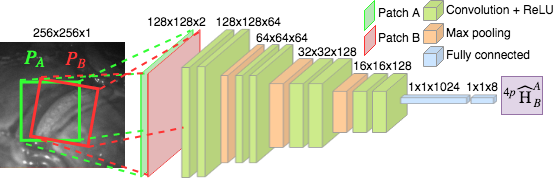

DIH [4] uses a VGG-like architecture, with 8 convolutional and 2 fully connected layers (Fig. 1). The input of the network is PA and PB, and output is their relative homography. Note that [4] used the MS-COCO dataset for training, where pair of patches were extracted from a single real image, free of artifacts (e.g. specular highlights, amniotic fluid particles) that appear in sequential data.

Mosaic from an image sequence can be generated by finding the pairwise homographies between adjacent frames, followed by computing the relative homographies with respect to a reference frame. The GT pairwise homographies are unknown in fetoscopic videos since they are captured from a monocular camera. Therefore, only through visualization, we can observe the error accumulated over time. For minimizing this error, in our proposed DSM, the relative homography is learned between patches that are extracted from a single image following the CDA (Sec. 3.1). Unlike [4], in practice homography is computed between two adjacent frames, having specular highlights and lack of texture, in fetoscopic videos. Therefore, testing by using pairs of patches from two adjacent frames results in varying . To overcome this error, we propose an outlier rejection step (Sec. 3.2) to improve the estimation. During testing (Fig. 2), we compute homographies between pairs of adjacent frames times by randomly selecting the location of PA. The estimated is converted to by applying Direct Linear Transform (DLT), followed by its decomposition using Singular Value Decomposition (SVD) and outlier rejection for removing inaccurate estimations.